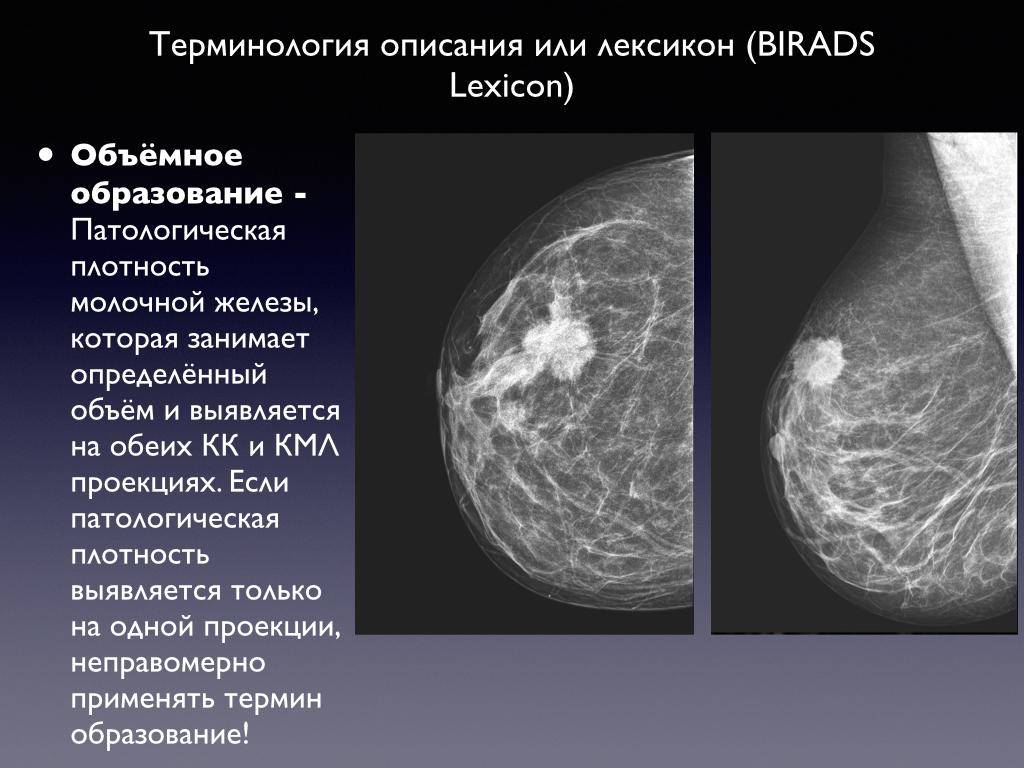

Научные исследования: Деформированные ядра и их свойства

Раздел: Визуальные истории